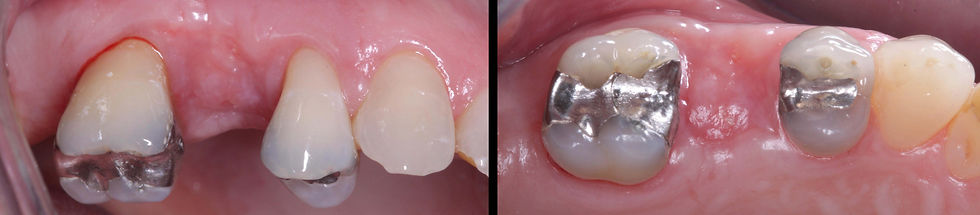

Initial clinical images of the crown on the 1.5.

Radiographic image of the crown on the 1.5. The periapical radiograph shows the radiolucent lesion around the third middle and apical of the root.